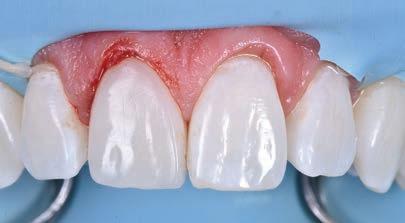

A 30-year-old patient, with a negative medical history, came to the clinic requesting the replacement of the previous composite reconstruction performed 10 years earlier following a trauma to UR1.

On clinical examination, UR1 was responsive to viability testing, and did not present periapical lesions on the radiograph performed on the same day (Figure 1). UR1 was discoloured and in a more palatal position than the contralateral central UL1 (Figure 2). The aesthetic analysis highlighted an asymmetry of the gingival zenith between UR1 and UL1. Through the use of a periodontal probe, after plexus anaesthesia, the altered passive eruption of the type IA junctional epithelium was confirmed according to the classification of Coslet et al. (Figure 3).

With a view to carrying out the most conservative restorative treatment possible on the patient, taking into account the age and vitality of the retained dental

FIGURE 1: Radiograph without periapical lesion.

element, it was decided to carry out a direct composite restoration following planning and a diagnostic wax-up of the case.

On the day of treatment, following local plexus anaesthesia, UR1 was isolated using a rubber dam, extending the isolation to the first premolars (Figure 4).

Subsequently, the fractured composite reconstruction was removed, a short bevel was performed on the preparation, and the entire surface of UR1 was sandblasted with 27 m aluminium oxide powder (Figure 5).

In order to correct the altered passive eruption, it was decided to recreate the emergence profile of the tooth by accentuating the vestibular bulge and seeking symmetry with the contralateral element. For this purpose, a pre-formed metal matrix was used and was blocked with two wedges. Once the matrix had been adapted, the adhesion procedures were carried out with a three-step etch and

FIGURE 2: Discolouration and palatal position of UR1.

FIGURE 3: The aesthetic analysis shows an asymmetry of the gingival zenith.

FIGURE 4: Isolation of UR1 with rubber dam.